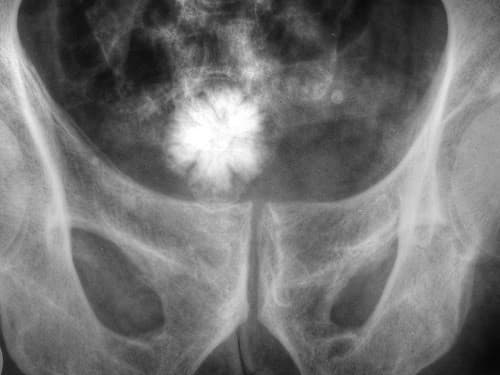

- Chụp X quang vùng chậu hông thấy có hình sỏi bàng quang.